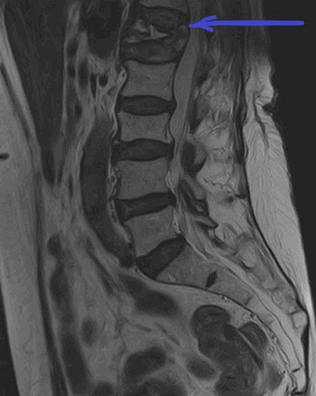

(Справа) При МРТ в сагиттальной плоскости в режиме STIR визуализируется изолированный перелом кубовидной кости, возникший вследствие избыточного отведения стопы. Следует отметить ступенеобразную деформацию суставной поверхности предплюсне-плюсневого сустава и ушиб сухожилия длинной малоберцовой мышцы.

4. МРТ при переломе кубовидной кости:

• Преимущества аналогичны КТ, однако МРТ позволяет обнаружить еще и отек костного мозга

• Используется для выявления стресс-переломов

• Позволяет оценить состояние сухожилия длинной малоберцовой мышцы:

о Проходит в одноименной борозде кубовидной кости, может повреждаться при переломе последней

(Справа) У этого же пациента при КТ в коронарной плоскости визуализируются вертикально ориентированные переломы кубовидной и ладьевидной костей. Изолированные переломы кубовидной кости встречаются редко, чаще они сочетаются с переломами прочих костей стопы. (Слева) У конькобежца при МРТ в сагиттальной плоскости на Т1ВИ определяется стресс-перелом кубовидной кости. Типичным для такого типа перелома является наличие в кости множества трещин, расходящихся в стороны в виде звезды.

(Справа) У этого же пациента при МРТ в сагиттальной плоскости в режиме STIR большую часть кубовидной кости занимает обширная зона отека костного мозга. На фоне отека хорошо видны линии перелома.